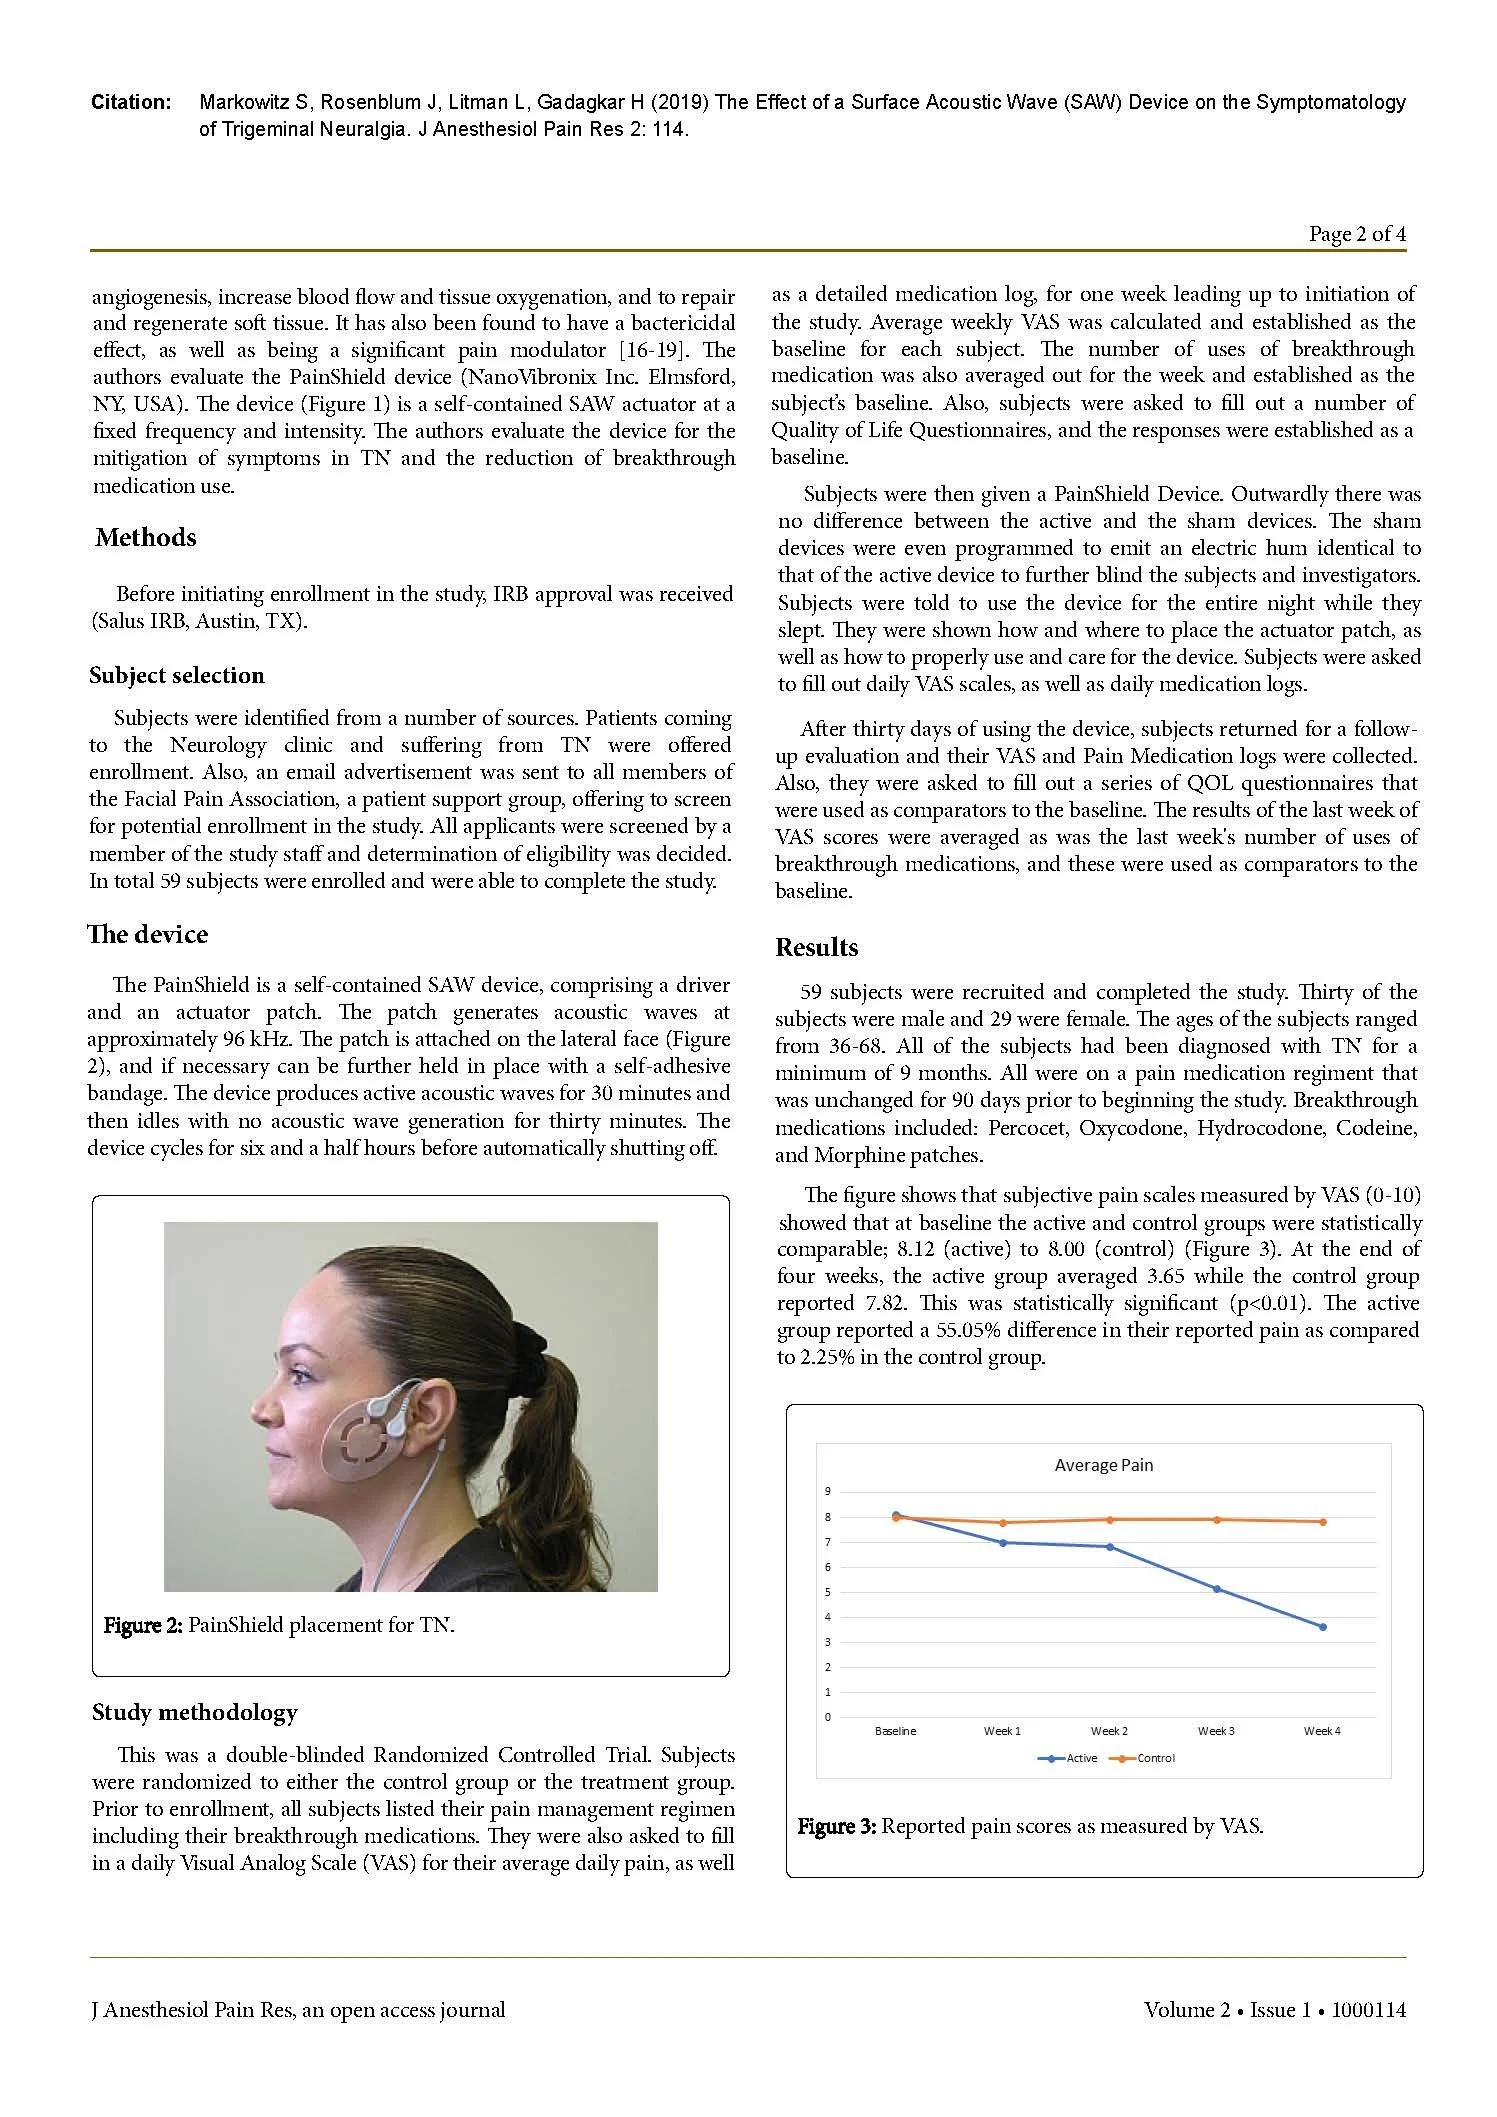

PainShield MD in the Treatment of Trigeminal Neuralgia.

A Historically Difficult to Treat Condition

Clinically Significant Pain Reduction as Measured by VAS 0-10. (1st generation device shown)